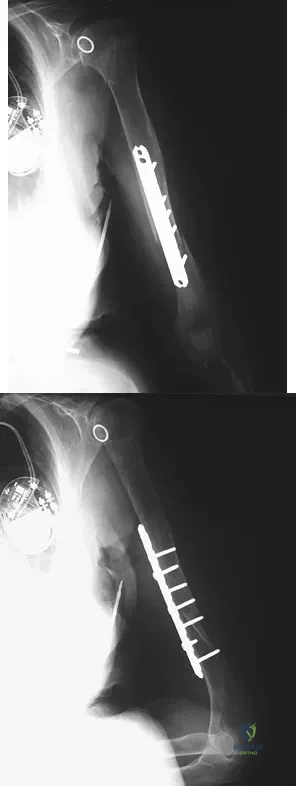

An 86-year-old woman sustained a fracture of the humerus and underwent surgical fixation 8 weeks ago. There was no radial nerve function below the elbow after surgery. Radiographs are shown in Figures 51a and 51b. What is the most appropriate management at this time?

An otherwise healthy 26-year-old woman is involved in a high speed motor vehicle accident and sustains the injury shown in Figure 54 to her dominant right arm. Appropriate treatment of this injury complex includes